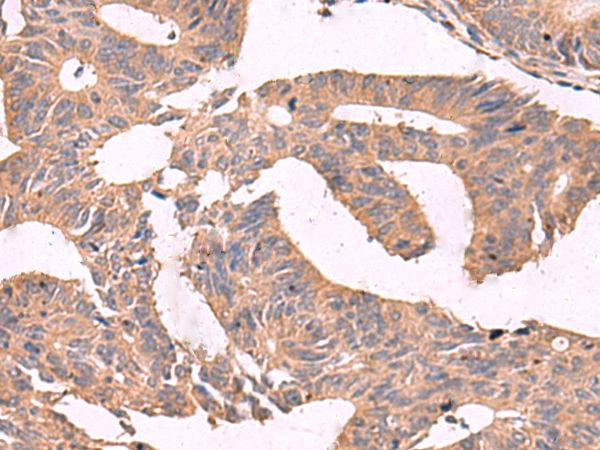

分类: 科研抗体货号: P09795别名: MCAK; CT139; KNSL6应用: IHC反应种属: Human, Mouse, Rat